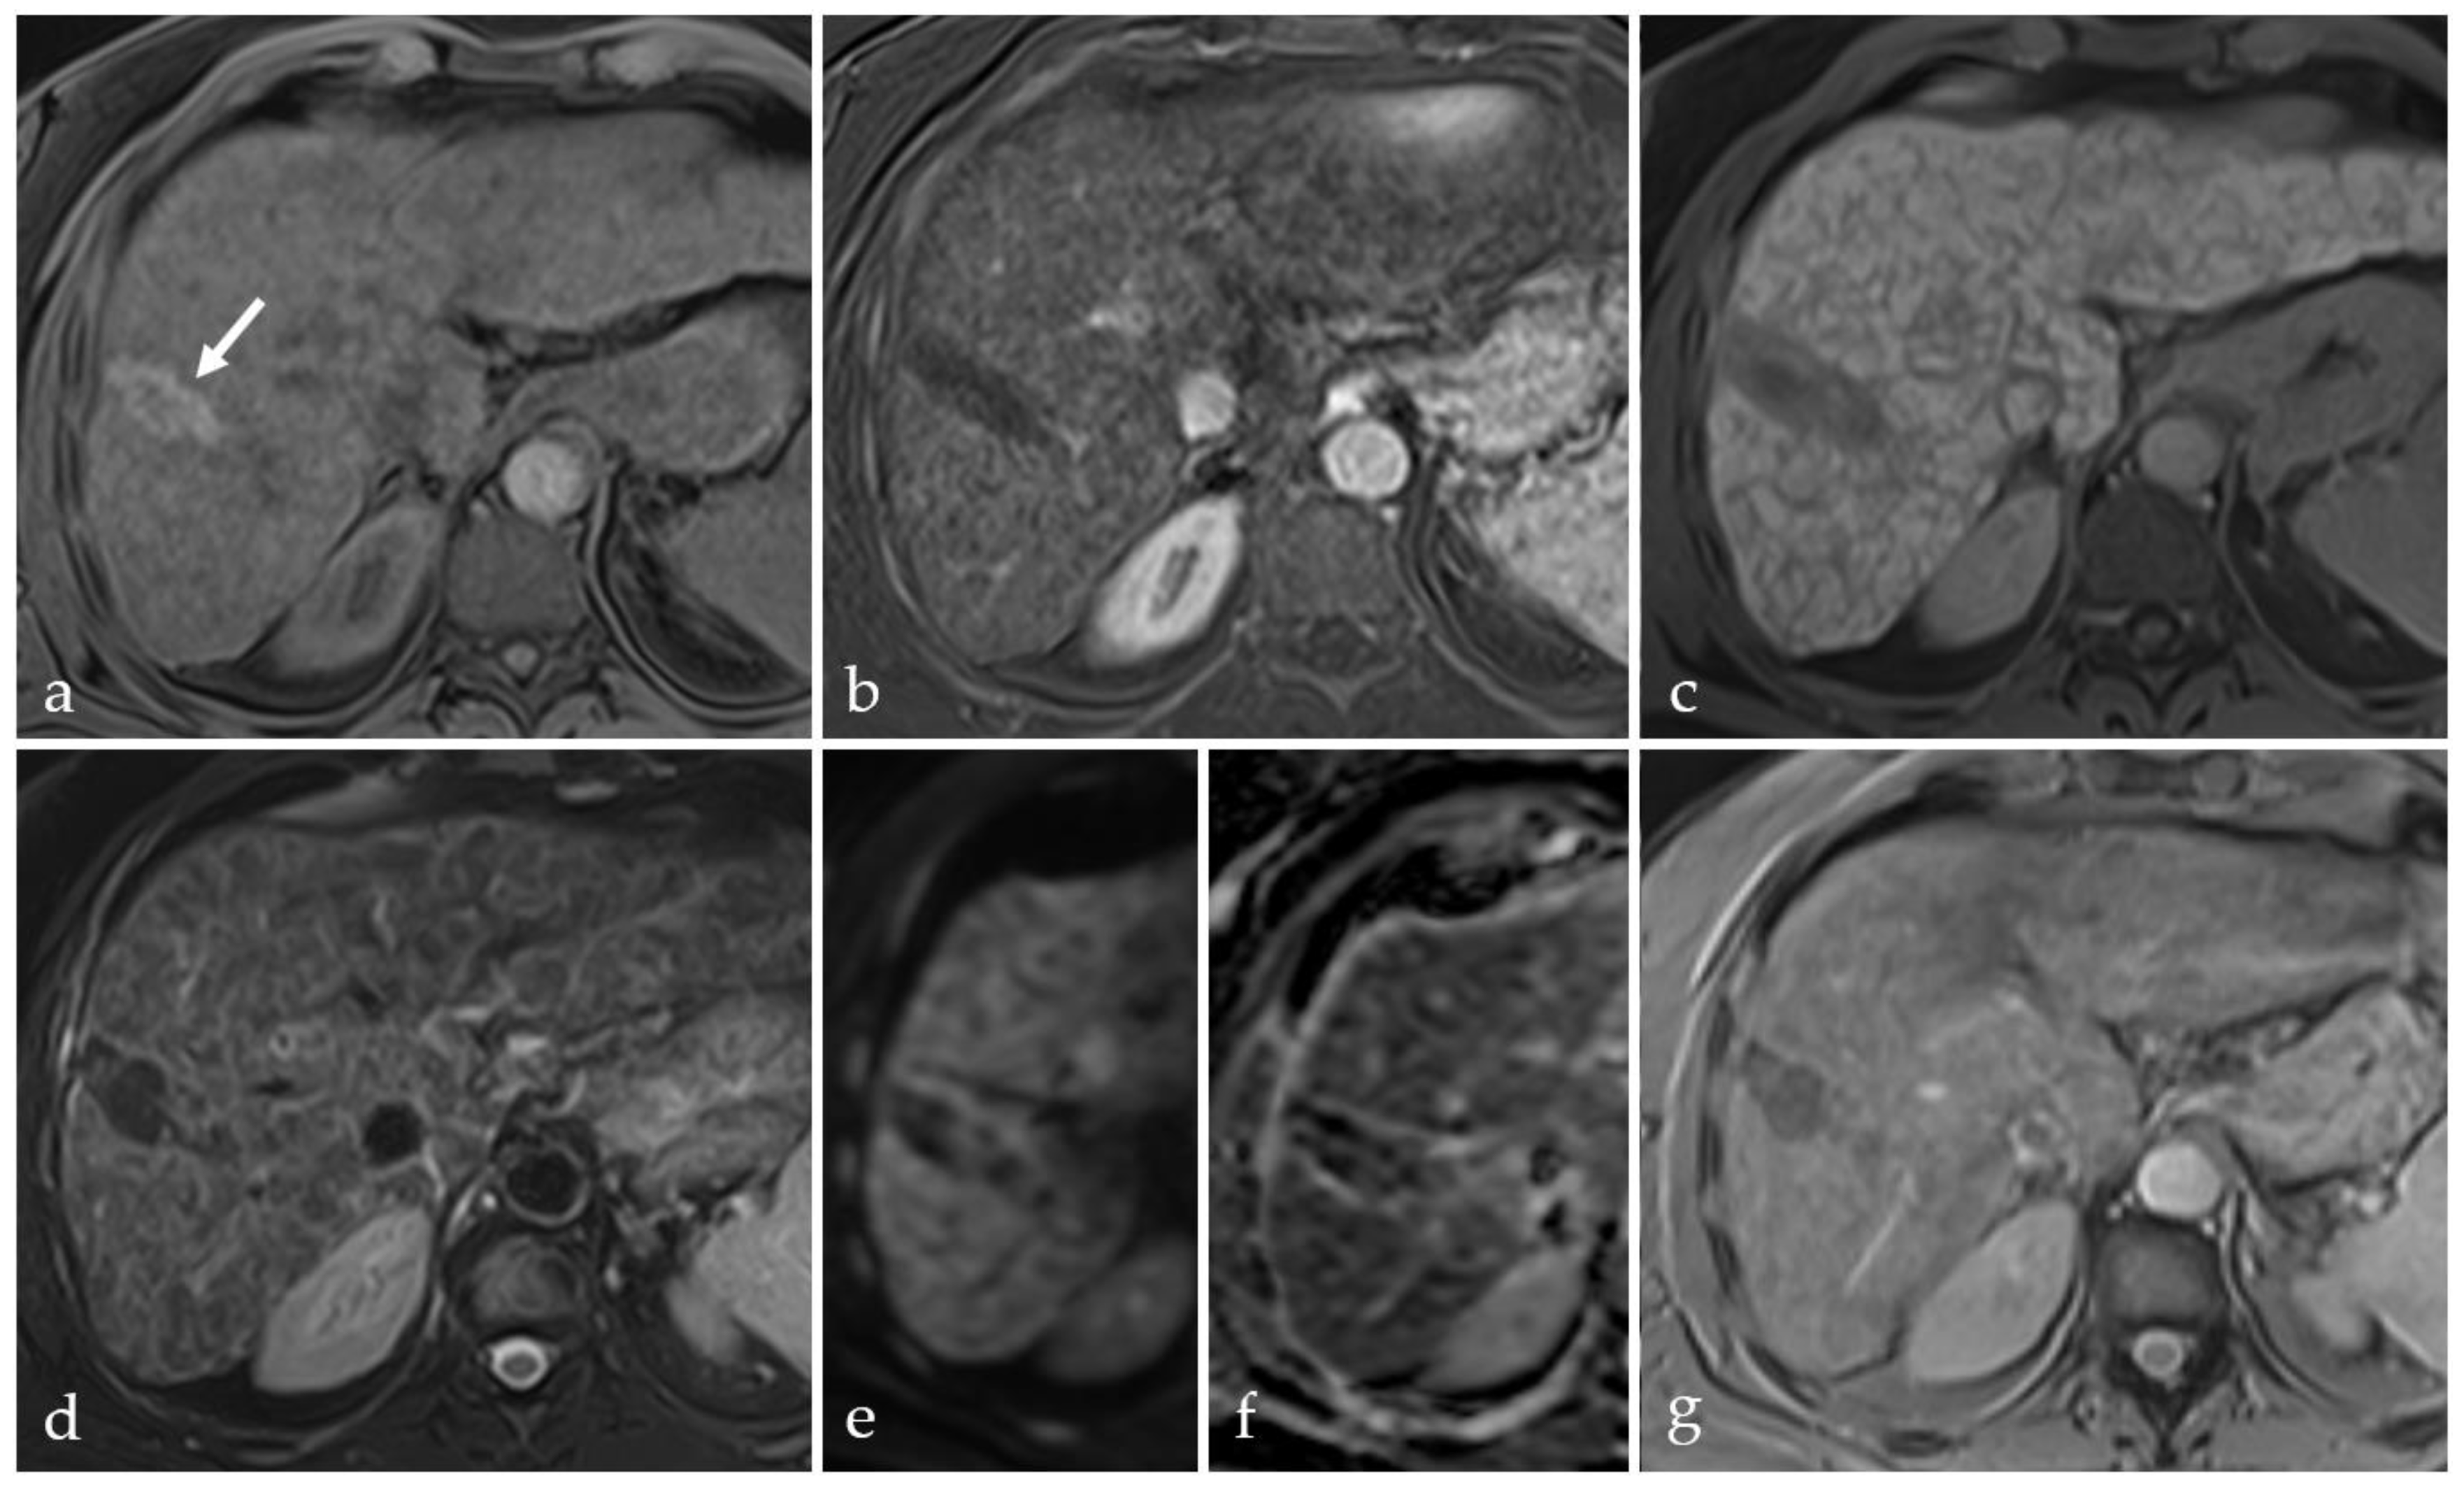

3.5. Post-Treatment Imaging Features of Tumor Viability